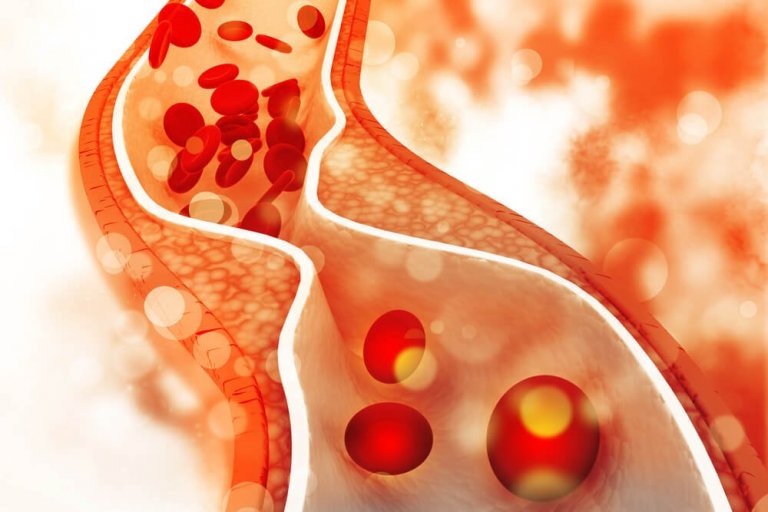

콜레스테롤이란?

콜레스테롤 조절에 도움이 되는 식단을 자세하게 알아보기 전에 이 물질이 간에서 생성된다는 것을 알고 있어야 한다. 콜레스테롤 수치는 신체 기능에 적절한 양의 지방을 세포에 제공한다. 문제는 품질이 낮은 지방을 섭취했을 때 발생한다. 이렇게 되면 콜레스테롤의 품질이 낮을 뿐만 아니라 세포가 필요로 하는 영양분도 얻지 못하게 된다.